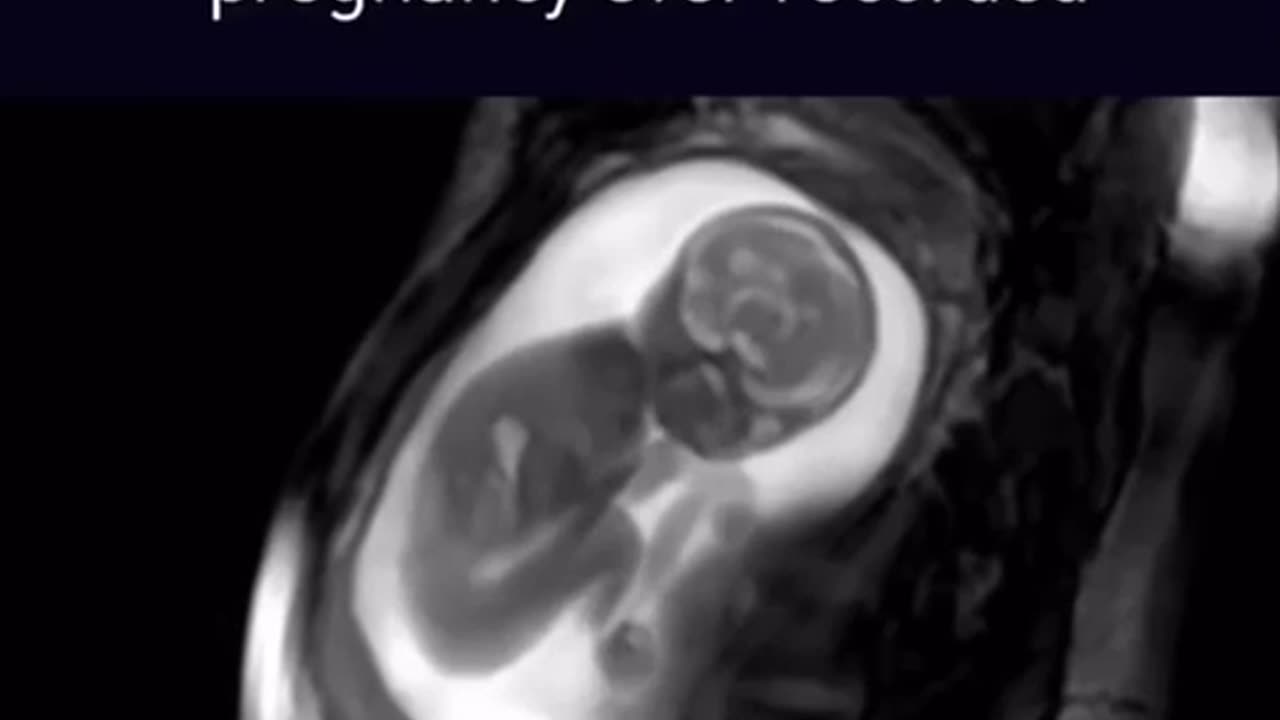

MRI: 5 months